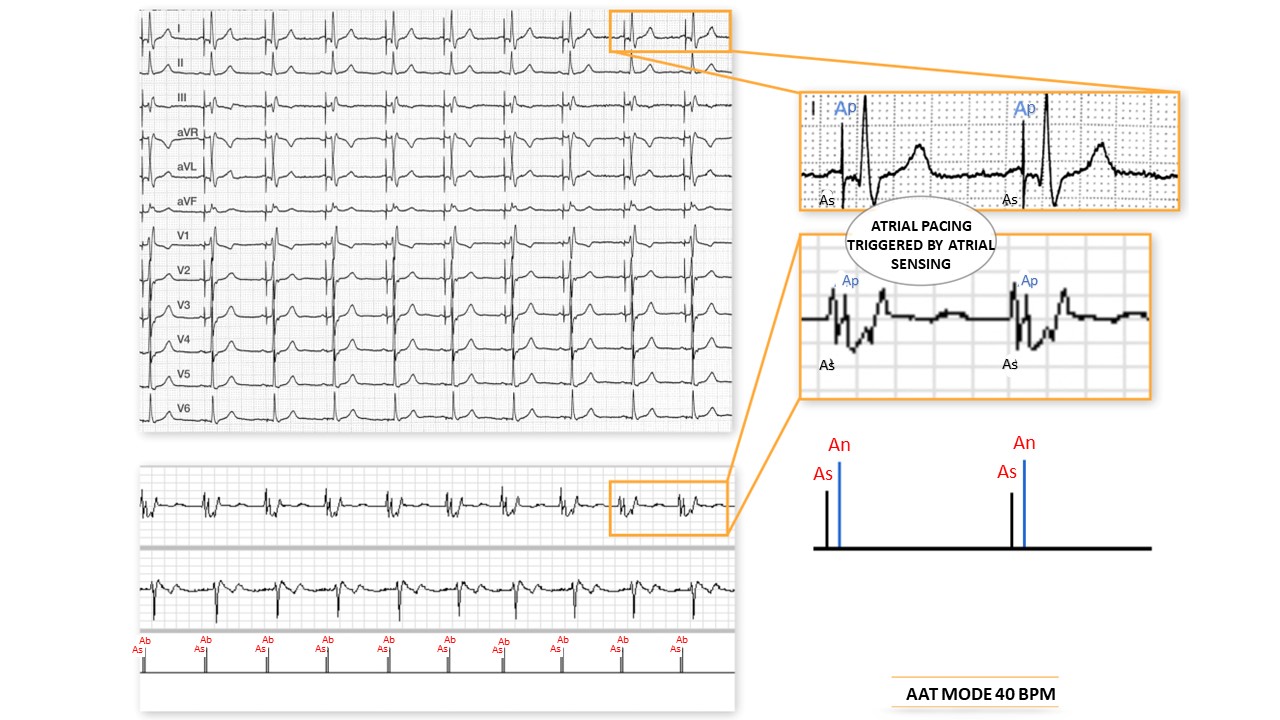

AAT mode 40 beats/minute: on this tracing, one can observe atrial pacing (An) triggered by atrial sensing (As); intrinsic ventricular activation;

Typical electrocardiographic pattern (AAT): the same for the atrium. The triggered modes can be used in 2 particular instances: 1. upon sensing myopotentials or electromagnetic interference, the SST does not inhibit but rather induces pacing on each artifact sensed outside the refractory period. This avoids a pause in pacemaker-dependent patients. To prevent runaway pacing, it is possible to either extend the refractory period or to limit the maximum pacing rate depending on the model. This type of mode was of interest on older pacemaker models that were more sensitive to external interference since they only worked in unipolar mode. 2. this mode is used to evaluate sensing in the chamber under consideration, to verify that there is no crosstalk and that the extrasystoles are also properly sensed. sensing is associated with an unnecessary increase in energy can be used temporarily to avoid inhibition in a pacemakerto monitor the sensing quality during temporary tests.